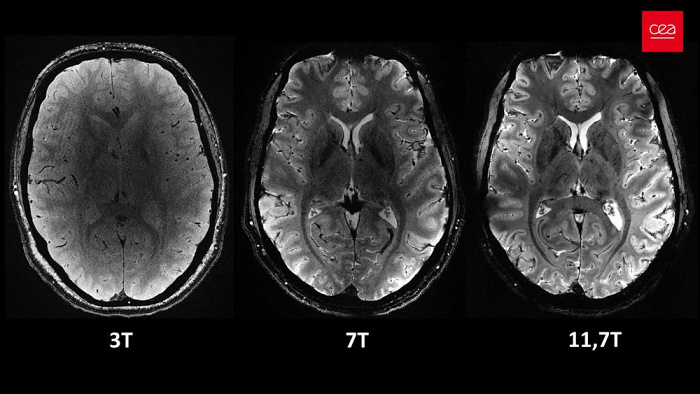

Самый мощный в мире МРТ-аппарат Iseult в несколько раз превзошел конкурентов

Во Франции разработан самый мощный в мире МРТ-аппарат под названием Iseult, который способен создавать магнитное поле с интенсивностью вплоть до 11,7 тесла. Это значительно превосходит возможности традиционных МРТ-сканеров, используемых в современных клиниках.

Основным преимуществом Iseult является его способность выполнять сканирование мозга с невероятно высоким разрешением. Всего за 240 секунд этот аппарат способен создать изображения мозга человека с толщиной срезов всего в 1 миллиметр. В то время как обычному МРТ потребовалось бы два часа для достижения подобных результатов, при этом пациент должен был бы находиться неподвижно.

Несколько лет назад Iseult проходил испытания на тыквах, а сейчас его успешно протестировали на 20 добровольцах. Полученные изображения демонстрируют все возможности этой технологии МРТ и способствуют более глубокому пониманию работы мозга. Помимо этого, этот мощный томограф может быть полезен не только ученым, но и медикам. С его помощью можно изучать и диагностировать нейродегенеративные заболевания, такие как болезнь Паркинсона и болезнь Альцгеймера.

Сообщается, что Iseult весит 132 тонны и имеет размеры 5 на 5 метров, а внутри него установлено 183 километра сверхпроводящих кабелей. Для охлаждения магнитов до рабочей температуры -271,35 °C требуется 7500 литров сжиженного гелия. О стоимости устройства нет информации, однако очевидно, что она очень высока. Новый МРТ-аппарат, предлагающий уникальные возможности, может появиться в некоторых передовых научных учреждениях в ближайшие годы.